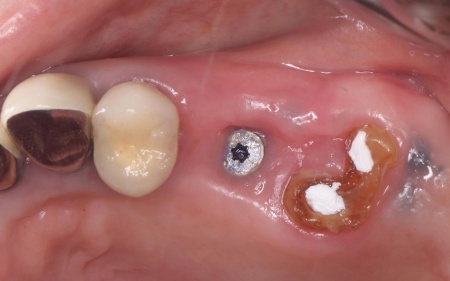

70代女性 折れた歯を抜いてインプラント治療で噛み合わせを回復した症例

拝見したところ、左上奥歯(第2小臼歯)1本が折れ、歯根だけの状態になっていました。

まず、左上奥歯を抜きます。

続いて、不足している骨を補強しつつ、インプラントを埋入した土台を安定させるための骨補填を行いました。

3ヶ月後、顎の骨の状態が良好であることを確認し、インプラントを埋入する手術を実施しました。